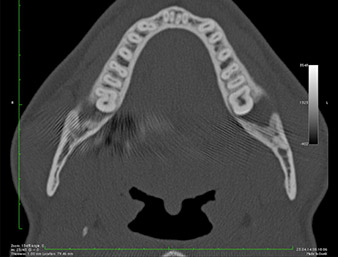

In der 3D-Aufnahme (digitales Volumentomogramm) war ersichtlich, dass sich der Wurzelrest weit disto-kaudal im Übergang vom horizontalen zum aufsteigenden Anteil des Unterkiefers befand (Abb. 2).

DVT-Darstellung

Abb. 2: Transversale DVT-Darstellung des Wurzelrests im retromolaren Raum

Unser Patient besaß anamnestisch gute Voraussetzungen (Nichtraucher, 26 Jahre) für einen erfolgreichen Eingriff. Wegen des Hinweises auf enge Lagebeziehung des Wurzelrestes zum N. alveolaris inferior in der Panoramaschicht-Aufnahme wurde zusätzlich eine digitale Volumentomografie erstellt (6).